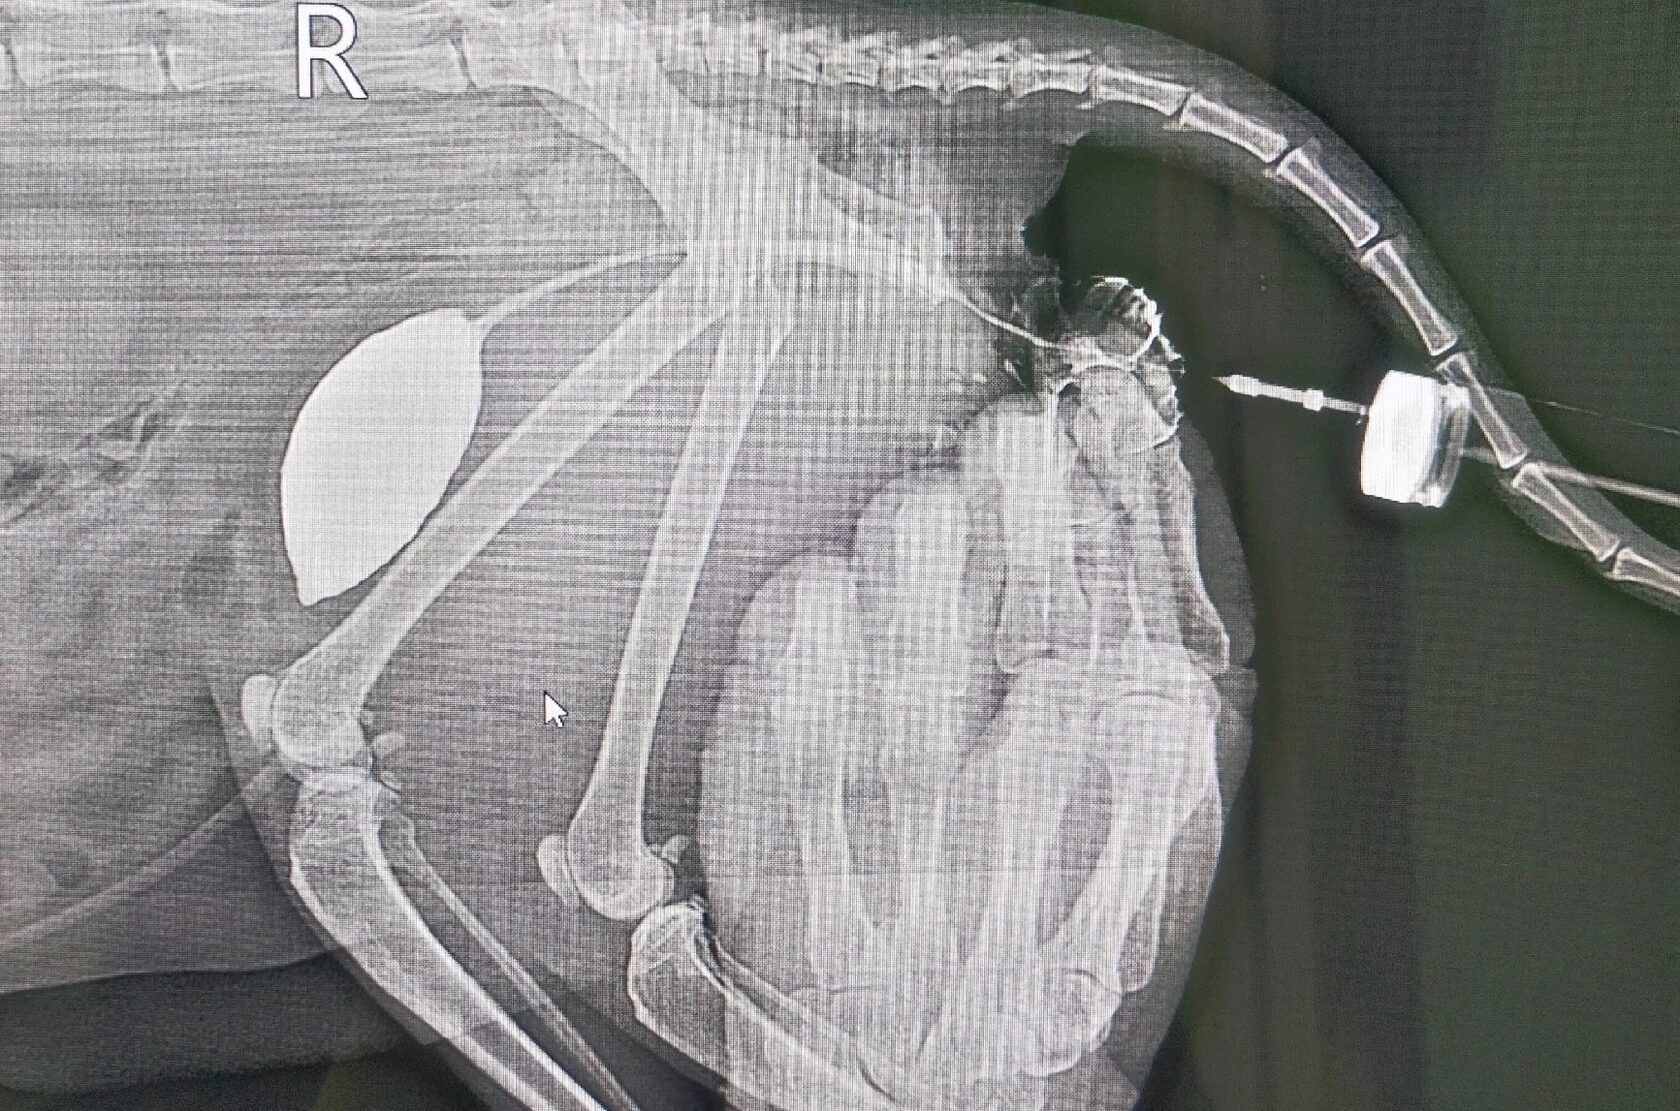

Стриктура полового члена - опасное расстройство, которое приводит к задержке мочи.

Поставить окончательный диагноз может рентгенография с введением контрастного вещества, как показано на данном фото.

В нашей клинике проводится подобное исследование. Если стриктура частично проходимая или непроходимая, то прибегают к оперативному вмешательству - промежностной уретростомии.